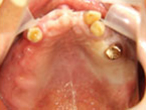

Case.01 骨造成インプラント治療症例

初診時

上下顎に数本の歯が残っていますが咬合支持がほとんどないために満足に食事もできない状態でした。また、下顎前歯部から臼歯部にかけて骨吸収が進行しており、上顎臼歯部にインプラント治療を行うためには骨造成が必要な状態です。

上顎

下顎